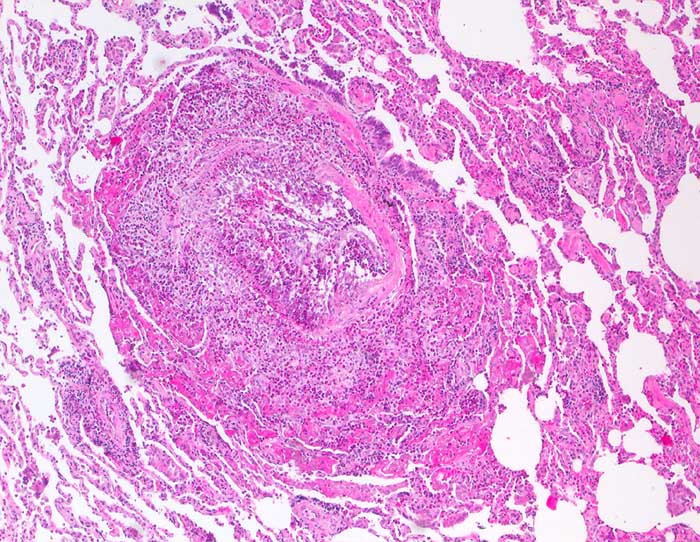

PathoPic – image database / PathoPic ID 6326 - Churg Strauss Vaskulitis

Churg Strauss Vaskulitis

Destruktive eosinophile Vaskulitis einer kleinen Arterie.

V.a. Churg-Strauss bei diffuser Lungeninfiltration bds, mehrjährigem Asthma mit aktueller Bluteosinophilie und IgE-Erhöhung. St.n. Therapie mit Leukotrien-Rezeptorantagonisten. Verschlechterung des Asthmas unter Therapie. -> diagnostische Thorakotomie.

Der morphologische Befund ist klassisch für ein Churg-Strauss-Syndrom und passt auch zu der Anamnese eines mehrjährigen Asthmas mit aktueller Bluteosinophilie und IgE-Erhöhung. Der Befund könnte im Zusammenhang stehen mit einer ca. seit drei Monaten bestehenden Therapie mit Leukotrien-Rezeptorantagonisten, welche nach Berichten aus der Literatur ein Churg-Strauss-Syndrom möglicherweise demarkieren können.

100